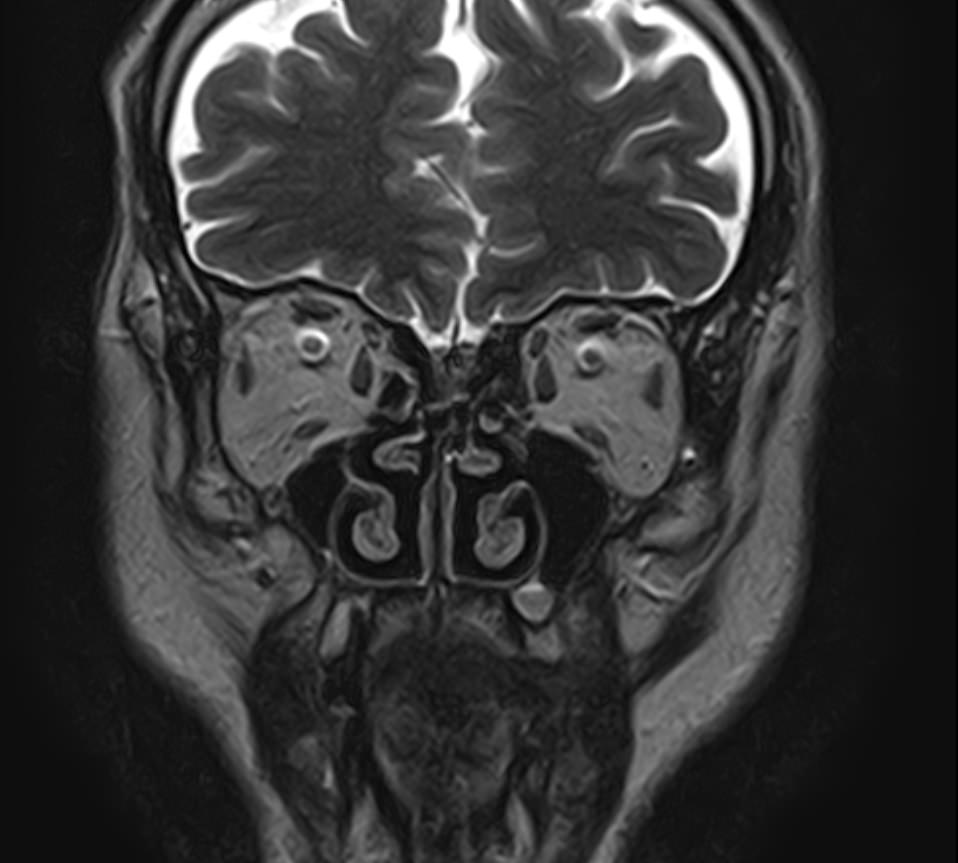

Придаточные пазухи носа представляют собой воздухоносные полости, которые располагаются в костях лицевого и мозгового черепа, выстланы изнутри слизистой оболочкой и сообщаются с полостью носа. МРТ является неинвазивным безопасным информативным способом визуализации данных анатомических областей. Метод позволяет диагностировать различные патологические процессы в области придаточных пазух носа.

Реализацию МРТ пазух носа предписывают, когда другие способы обследования больного не дают полную диагностическую картину. Это необходимо, когда нужны данные о состоянии сложно доступных клиновидных или решетчатых пазух, расположенных за костно-хрящевыми структурами черепа.

Снимки, полученные в ходе магнитно-резонансной томографии, дают подробные данные о:

• патологиях формирования пазух и полости носа;

• аномалиях строения костно-хрящевых структур;

• травмах лицевой части черепа — переломах, смещениях костных фрагментов;

• утолщениях костных стенок и слизистых оболочек;

• кистозных и опухолевых образованиях;

• злокачественных новообразованиях даже на самых начальных стадиях;

• степени симметричности околоносовых полостей;

• скоплении крови или иных жидкостей в придаточных пазухах носа.